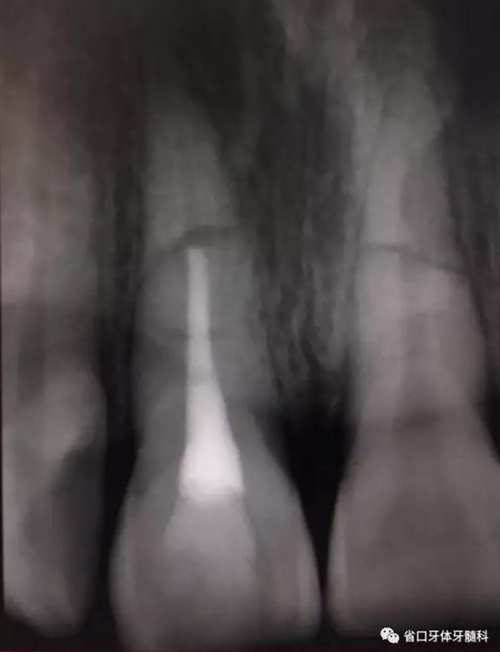

圖6 斷端MTA封閉術(shù)后

處理:11橡皮障隔濕,顯微鏡下開(kāi)髓,揭髓室頂,K銼疏通根管,拔髓,測(cè)長(zhǎng)度(到根折斷端處)17mm,顯微鏡下鎳鈦預(yù)備根管,按工作長(zhǎng)度預(yù)備根管至60#,沖洗根管,吸干,顯微鏡下MTA斷端封閉,髓腔內(nèi)放置半飽和蒸餾水棉球一個(gè),玻璃離子臨時(shí)充填。